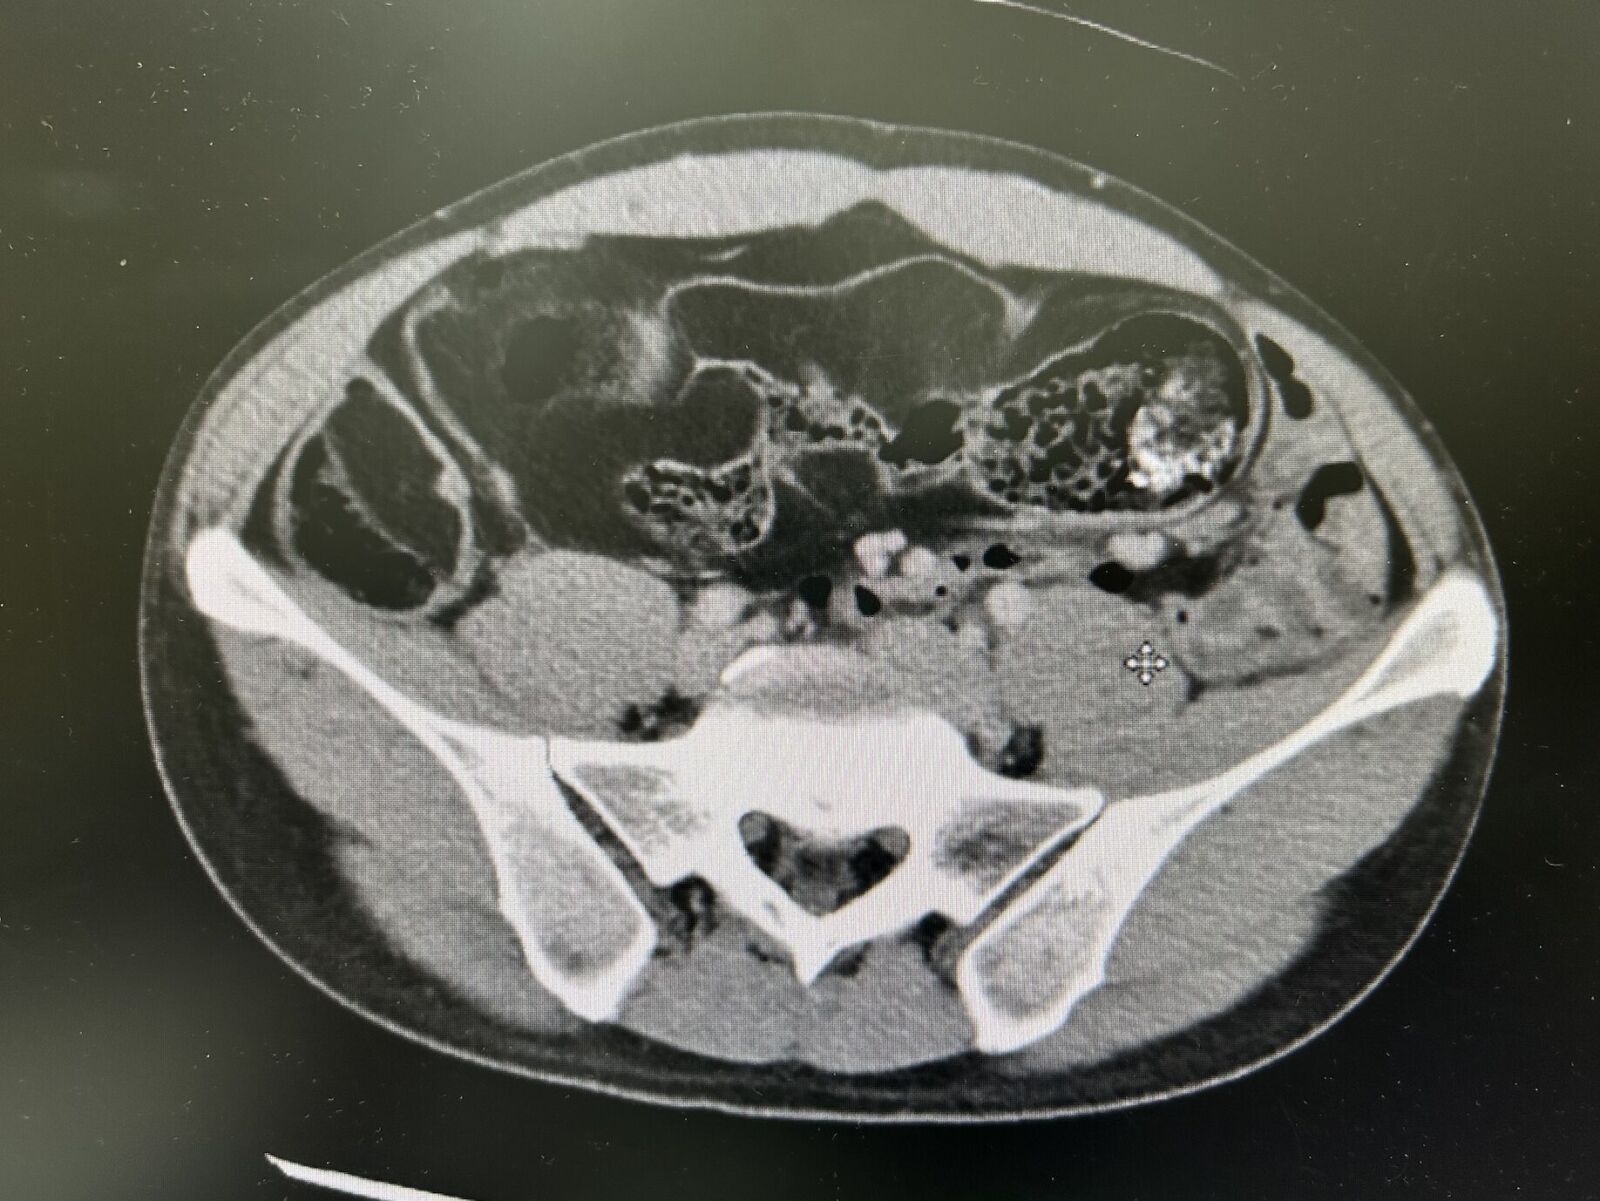

▲檢查發現男子腹部右側及中間部位布滿多發性脂肪瘤。

男子在經過電腦斷層掃描檢查之後,果然發現腹腔內多處低回音腫塊,並合併嚴重腸道糞便滯留,初步懷疑為「惡性腹腔脂肪肉瘤」,經多專科團隊會診後,決定採剖腹探查。